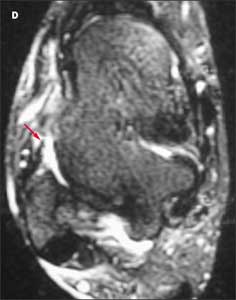

Because the patient’s pain is severe, you order an MRI scan to further evaluate the injury. A T2-weighted axial image reveals disruption of the anterior talofibular ligament (D, red arrow).

This patient has a grade 3 injury to the anterior talofibular ligament. In another axial T2-weighted image (E), fluid (yellow arrow) is visible in and around the course of the ligament (red arrow). This confirms that the disruption is acute. The posterior talofibular ligament appears normal and intact (E, orange arrow).

Patients with injuries of this ligament often do not seek medical attention, and it can be difficult to distinguish between acute and more remote injuries on imaging studies. Acute tenderness and fluid at the site of the disruption are 2 clues that can help identify an acute injury.